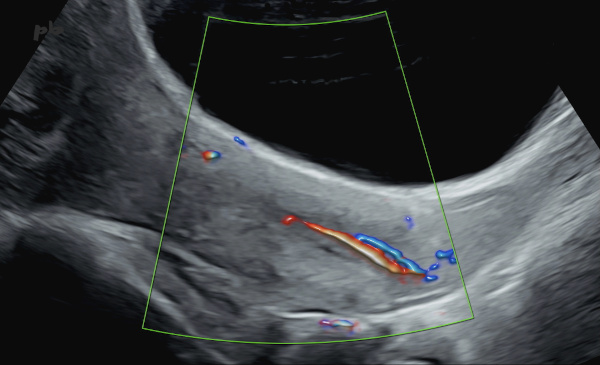

8 – Polype endocervical

Grossesse de 18SA.

Echographie par voie sus-pubienne – coupe sagittale centrée sur le col.

Visualisation d’une image de pédicule vasculaire en doppler couleur dans la lumière cervicale.